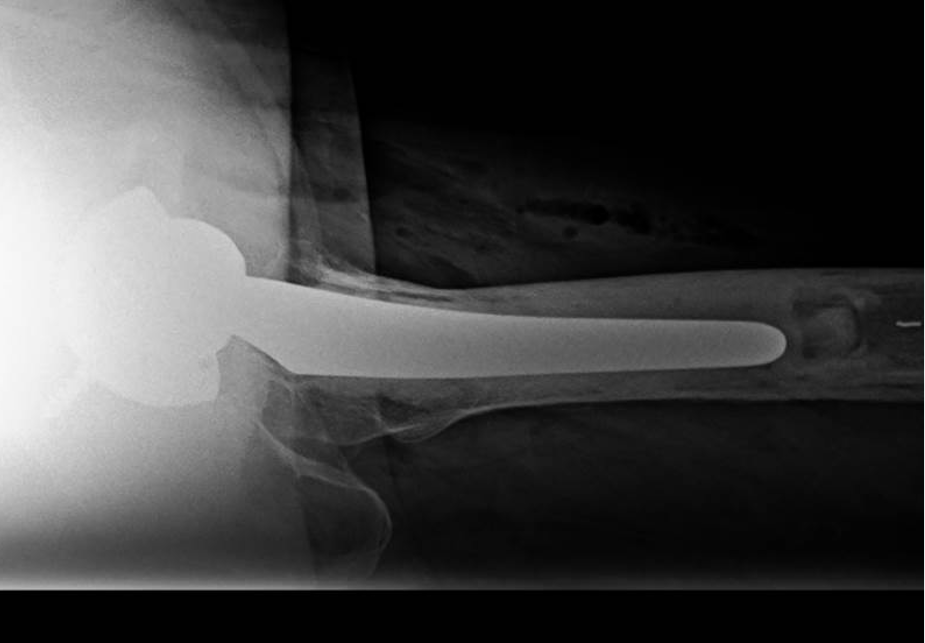

〈手術後のレントゲン〉(側面)

当院にて人工股関節全置換術(THA)を施行。アプローチはAMIS(前方最小侵襲手術)で行い、術後は強い痛みを訴えることもなく、術翌日より歩行器歩行を開始しスムーズにリハビリをすすめられました。

アプローチはAMIS(前方最小侵襲手術)で行い、翌日から歩行器での歩行訓練を開始。

術後2日目には杖なしでの歩行、術後4日目で階段昇降が可能となり、術後1週間程で退院となりました。